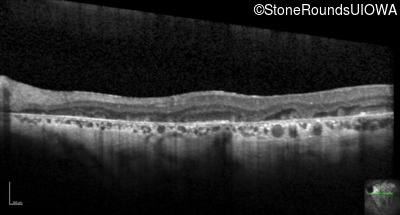

Optical Coherence Tomography - Left - 20/200

Exemplar / OCT Stack